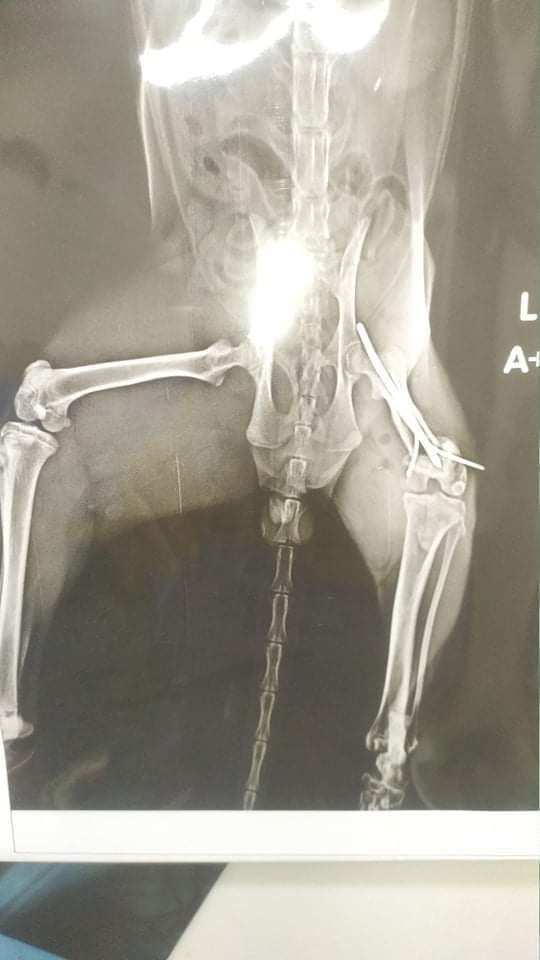

وقال الدكتور القصبي، في بيان له، إن صاحبة الحالة توجهت لأكثر من عيادة بيطرية، لإنقاذ القطة وكانت جميع التوصيات بـ"بتر القدم"، مضيفا أنه فور وصول الحالة للمركز الخاص بالحيوانات الأليفة ببنها، تم الكشف والفحص الطبي بدقة على "سيمبا "، واتخاذ القرار بالتدخل الجراحى العاجل وذلك بإجراء عملية جراحية لتثبيت الكسور بالرجل والفخذ، عن طريق تثبيت المسمار النخاعي والمسامير الجانبية، وتم تخديرها للتدخل الجراحي واستغرقت العملية 120 دقيقة.

وأكد القصبي أن قرار إنقاذ القطة وتركيب المسامير جاء لإنقاذها من فقد رجلها للأبد، وأوضح أن القطة بصحة جيدة وبدأت تسير بشكل طبيعي، وتم إزالة المسامير أول أمس وعادت قدمها للوضع الطبيعي.